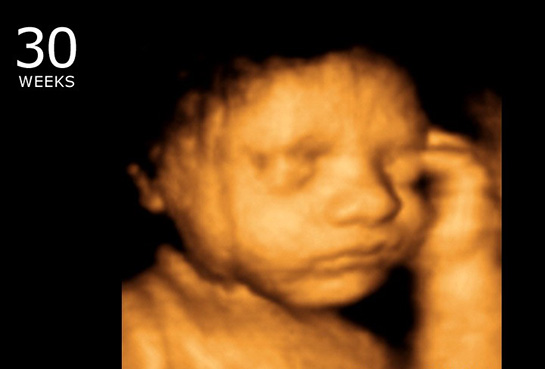

10 haftalık gebelik, hamileliğin ikinci trimesterine geçişin başlangıcını işaret eden önemli bir dönemdir. Bu dönemde, fetüs hızla gelişmekte ve anne vücudunda çeşitli değişiklikler meydana gelmektedir. Bu makalede, 10 haftalık gebeliğin fiziksel ve psikolojik etkileri, fetal gelişim, beslenme önerileri ve dikkat edilmesi gereken noktalar üzerinde durulacaktır. Fetal Gelişim 10. hafta itibarıyla fetüs, yaklaşık 3,5 cm uzunluğundadır ve bu haftada önemli gelişim aşamalarından geçmektedir. Aşağıda fetüsün bu aşamadaki gelişimsel özellikleri sıralanmıştır: